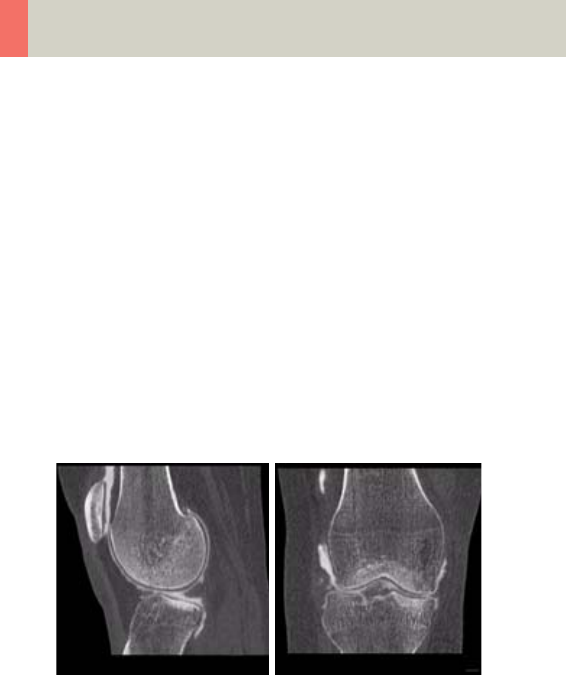

Lower Extremities 346

- Knee 350

- Foot 352